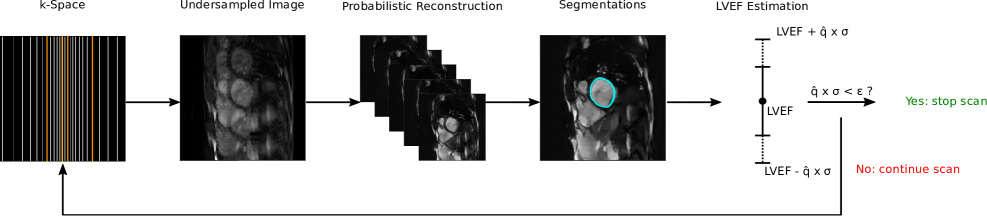

We propose a dynamic acquisition pipeline that iterates over a set of undersampling rates, assesses the uncertainty of derived clinical metrics and stops the scan once a predefined confidence threshold is reached. The pipeline operates as follows: after each k-space acquisition step, we first generate a set of plausible reconstructions from the currently undersampled k-space data using a probabilistic reconstruction model, PHiRec [15], which we describe in Section 2.1. In Section 2.2 we showcase how to propagate uncertainty where each candidate reconstruction is segmented by a deterministic segmentation network, , yielding a set of segmentations , where . From these segmentations, a clinical metric of interest, , is computed via a function , resulting in a set of metric samples , where . In our experiments, these metrics are the left ventricular ejection fraction and patellar cartilage volume. We quantify the uncertainty of the metric by its empirical standard deviation, which is then calibrated using a scaling factor derived from conformal prediction (Section 2.3). This entire process—reconstruction, segmentation, metric estimation, and uncertainty calibration—is repeated after each acquisition step. The acquisition is terminated when the calibrated uncertainty bound falls below a user-defined threshold, . A schematic of this iterative process is provided in Figure 1.

After training the models and calibrating the uncertainties as described above, we evaluated our proposed framework in three steps. First, we quantified the performance of the underlying reconstruction and segmentation models in Section 4.1. In Section 4.2, we analyzed the behavior of the dynamic stopping mechanism, comparing outcomes with and without uncertainty calibration. Finally, we present qualitative examples to visualize the method’s performance in Section4.3.

4.2 Dynamic Stopping Behavior and Coverage

We next analyzed the behavior of the uncertainty-guided stopping mechanism, with quantitative results visualized in Figure 3. Our method successfully determines patient-specific scan durations; however, its effectiveness is critically dependent on calibration. Without calibration, the mechanism consistently terminated scans fairly early. For the SKM-TEA dataset, every scan was stopped at the highest acceleration factor (32x), while CINE scans stopped at an average of 13.2x. In contrast, applying conformal calibration resulted in significantly longer scan durations, with average stopping points of 4.35x for SKM-TEA and 8.3x for CINE.

This difference in stopping behavior directly translated to a substantial reduction in prediction error. For the SKM-TEA dataset, the average volume error at stopping decreased from 0.91 (uncalibrated) to 0.42 (calibrated). Similarly, for the CINE dataset, the average LVEF error was reduced from 16.5% (uncalibrated) to 5.90% (calibrated), underscoring the necessity of calibration for achieving reliable downstream predictions.

We next analyzed the behavior of the uncertainty-guided stopping mechanism. As shown in Figure 3, our method successfully determines patient-specific scan durations rather than relying on a fixed acquisition time. To assess the impact of calibration, we compared the distribution of stopping points determined by uncalibrated versus calibrated uncertainties. Without calibration, the mechanism consistently terminated scans fairly early. This was particularly pronounced for the SKM-TEA dataset, where every scan was stopped at the highest acceleration factor (32x). In contrast, applying conformal calibration resulted in significantly longer and more varied scan durations which showed an average stopping at 4.35x for the SKM-TEA dataset. Similarly, for the CINE dataset we observed an average stopping at 13.2x for the uncalibrated and 8.3x for the calibrated case. Additionally, we analyzed the error at stopping which can be seen in Figure 3. For both datasets, the error at stopping was higher in the uncalibrated compared to the calibrated case. For the SKM-TEA dataset, the average error for the predictions at stopping in the uncalibrated case was 0.91 and 0.42 for the calibrated case. For the CINE dataset, the LVEF error for uncalibrated stops was on average 16.5% and for the calibrated case 5.90%.

To evaluate the statistical reliability of the uncertainty intervals at the moment of stopping, we measured the empirical coverage—the percentage of test cases where the ground truth metric fell within the predicted interval. For SKM-TEA, uncalibrated intervals achieved only 17.6% coverage, which increased to 61.1% after calibration. For the CINE dataset, coverage improved from 20.0% to 85.7% with calibration. While calibration substantially improved reliability, the empirical coverage for both datasets remained below the target of 90%.

The core contribution of this work lies in the dynamic stopping mechanism. The dramatic difference between uncalibrated and calibrated stopping points (Figure 3) reveals a critical insight: raw neural network uncertainties are not reliable proxies for model error. The uncalibrated models were consistently overconfident, terminating scans when the downstream metric error was still high (Figure 3). This misalignment poses a significant clinical risk. Conformal calibration corrects this by widening the uncertainty intervals to better reflect the true potential for error, leading to more appropriate and safer stopping decisions. This finding aligns with a growing body of literature emphasizing the necessity of calibration for deploying machine learning models in high-stakes medical applications [26, 41].

Furthermore, our qualitative results (Figures 4, 5) visually corroborate these quantitative findings. The clear correlation between wider uncertainty bands, visible image artifacts, and inaccurate segmentations provides intuitive evidence that the calibrated uncertainty is a meaningful and trustworthy indicator of quality.